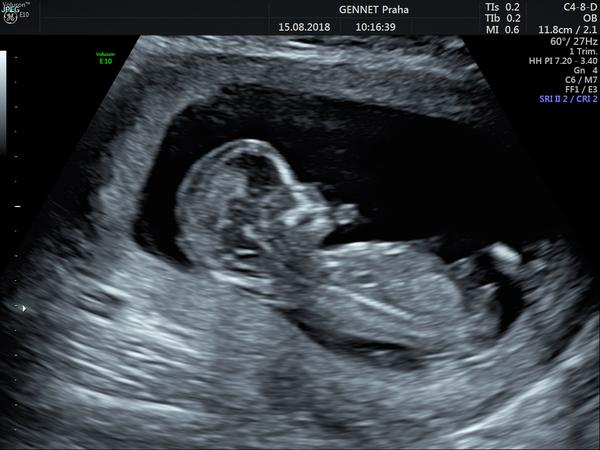

Ahoj holky, tak I. screening za mnou, výsledky celkem fajn 🙂 nosní kůstka přítomna, šíjové projasnění 1,5. Trizomie 21 = 1:39300 a ty ostatní dvě 1:50000 🙂 bylo to super!!! dostala jsem teda žádanku i na triply, ale prý jen jestli budu chtít, moc se mi na ně nechce...pohlaví nám ale nechtělo ukázat, schovávalo se 🙂